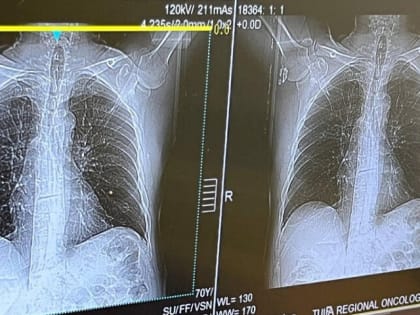

Онколог Моисеева: “Теперь мы не только выявили, но удалили и понаблюдали”

Малоинвазивные операции и высокоточные исследования – эндоскопическое отделение Тульского онкодиспансера вышло на новый уровень.